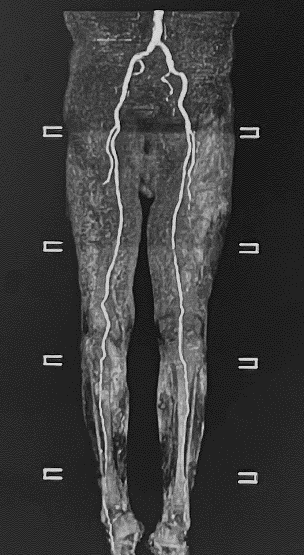

既に定評のある、脳神経、骨関節領域の他に、MRアンギオ(脳血管・四肢血管が描出可能)、MRCP(造影剤を用いない胆管・膵管画像)、急性期脳梗塞の診断(拡散強調像、MRアンギオや灌流画像を組み合わせることで治療方針の決定に有用)などの撮像法にも対応可能です。